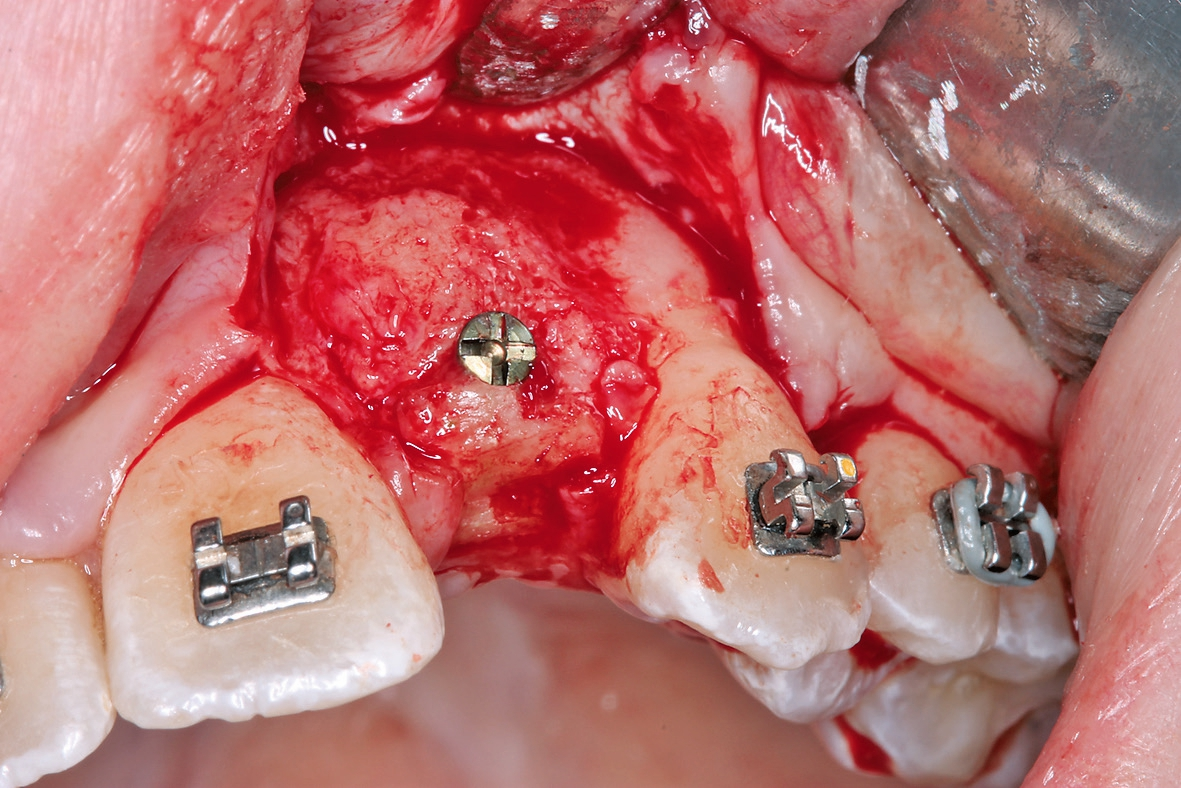

Eine 17-jährige Patientin wurde an unsere Praxis mit dem Wunsch nach einer festsitzenden implantatprothetischen Versorgung der lateralen Schneidezähne 12 und 22 überwiesen. Nach entsprechender Aufklärung und intensiver Beratung wurde zunächst ein DVT erstellt, um das genaue Ausmaß der dreidimensionalen Knochenresorption in regio der fehlenden lateralen Schneidezähne regio 12 und 22 beurteilen zu können. Die röntgenlogische Auswertung ergab eine hochgradige horizontale Alveolarfortsatzbreite von knapp 3 mm in regio 12 respektive von knapp 2,5 mm in regio 22 mit stark ausgeprägter konkaver Kontur der bukkalen Lamelle (Abb. 1). Allein das klinische Bild (Abb. 2 und 3) zeigte eine ausgeprägte horizontale Alveolarfortsatzatrophie in regio 12 und 22 mit ausgeprägten Konkavitäten in der bukkalen Lamelle.

Letztendlich bestand aus kieferorthopädischer Sicht keine Kontraindikation für eine unverzügliche chirurgische Intervention mit nachfolgender implantatprothetischer Versorgung bei derart fortgeschrittener horizontaler Atrophie in regio 12 und 22 (2,5 mm mit großer Konkavität). Insofern wurde nach erneuter intensiver dokumentierter Beratung und Aufklärung wie auch wirtschaftlicher Aufklärung nach entsprechender beidseitiger Leitungsanästhesie am Foramen infraorbitale und zusätzliche intraoralen und vestibulären Infiltrationsanästhesien zunächst ein breiter Mukoperiostlappen von regio 14 bis 24 gebildet (Abb. 4) und zur Förderung der Durchblutung des allogenen Transplantates wurden entsprechende Bleeding-Points (entsprechende Perforation der bukkalen Kortikalis) gesetzt (Abb. 5). Die mit Hilfe von CAD/CAM durch das Labor ProDent (Zahntechnikermeister Thomas Blaschke) hergestellten kortikospongiösen Blöcke nach DVT-Auswertung wurden mit entsprechenden Osteosyntheseschrauben fixiert (Abb. 6) und mögliche Restspalträume mit allogener Spongiosa abgedichtet und lateral auskonturiert.